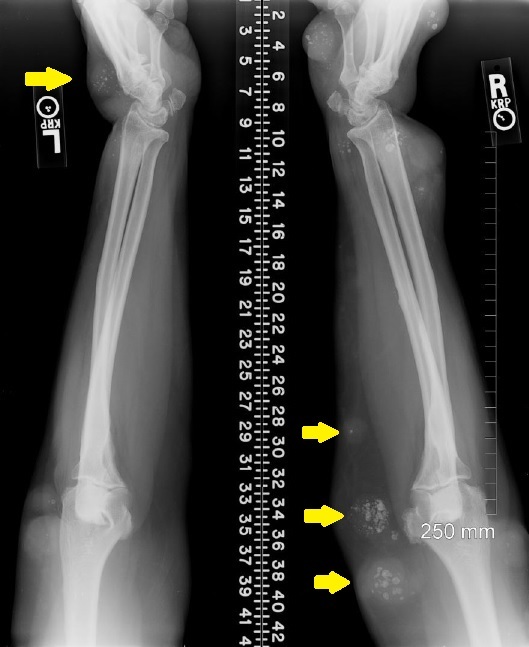

Identify

Soft tissue hemangiomas